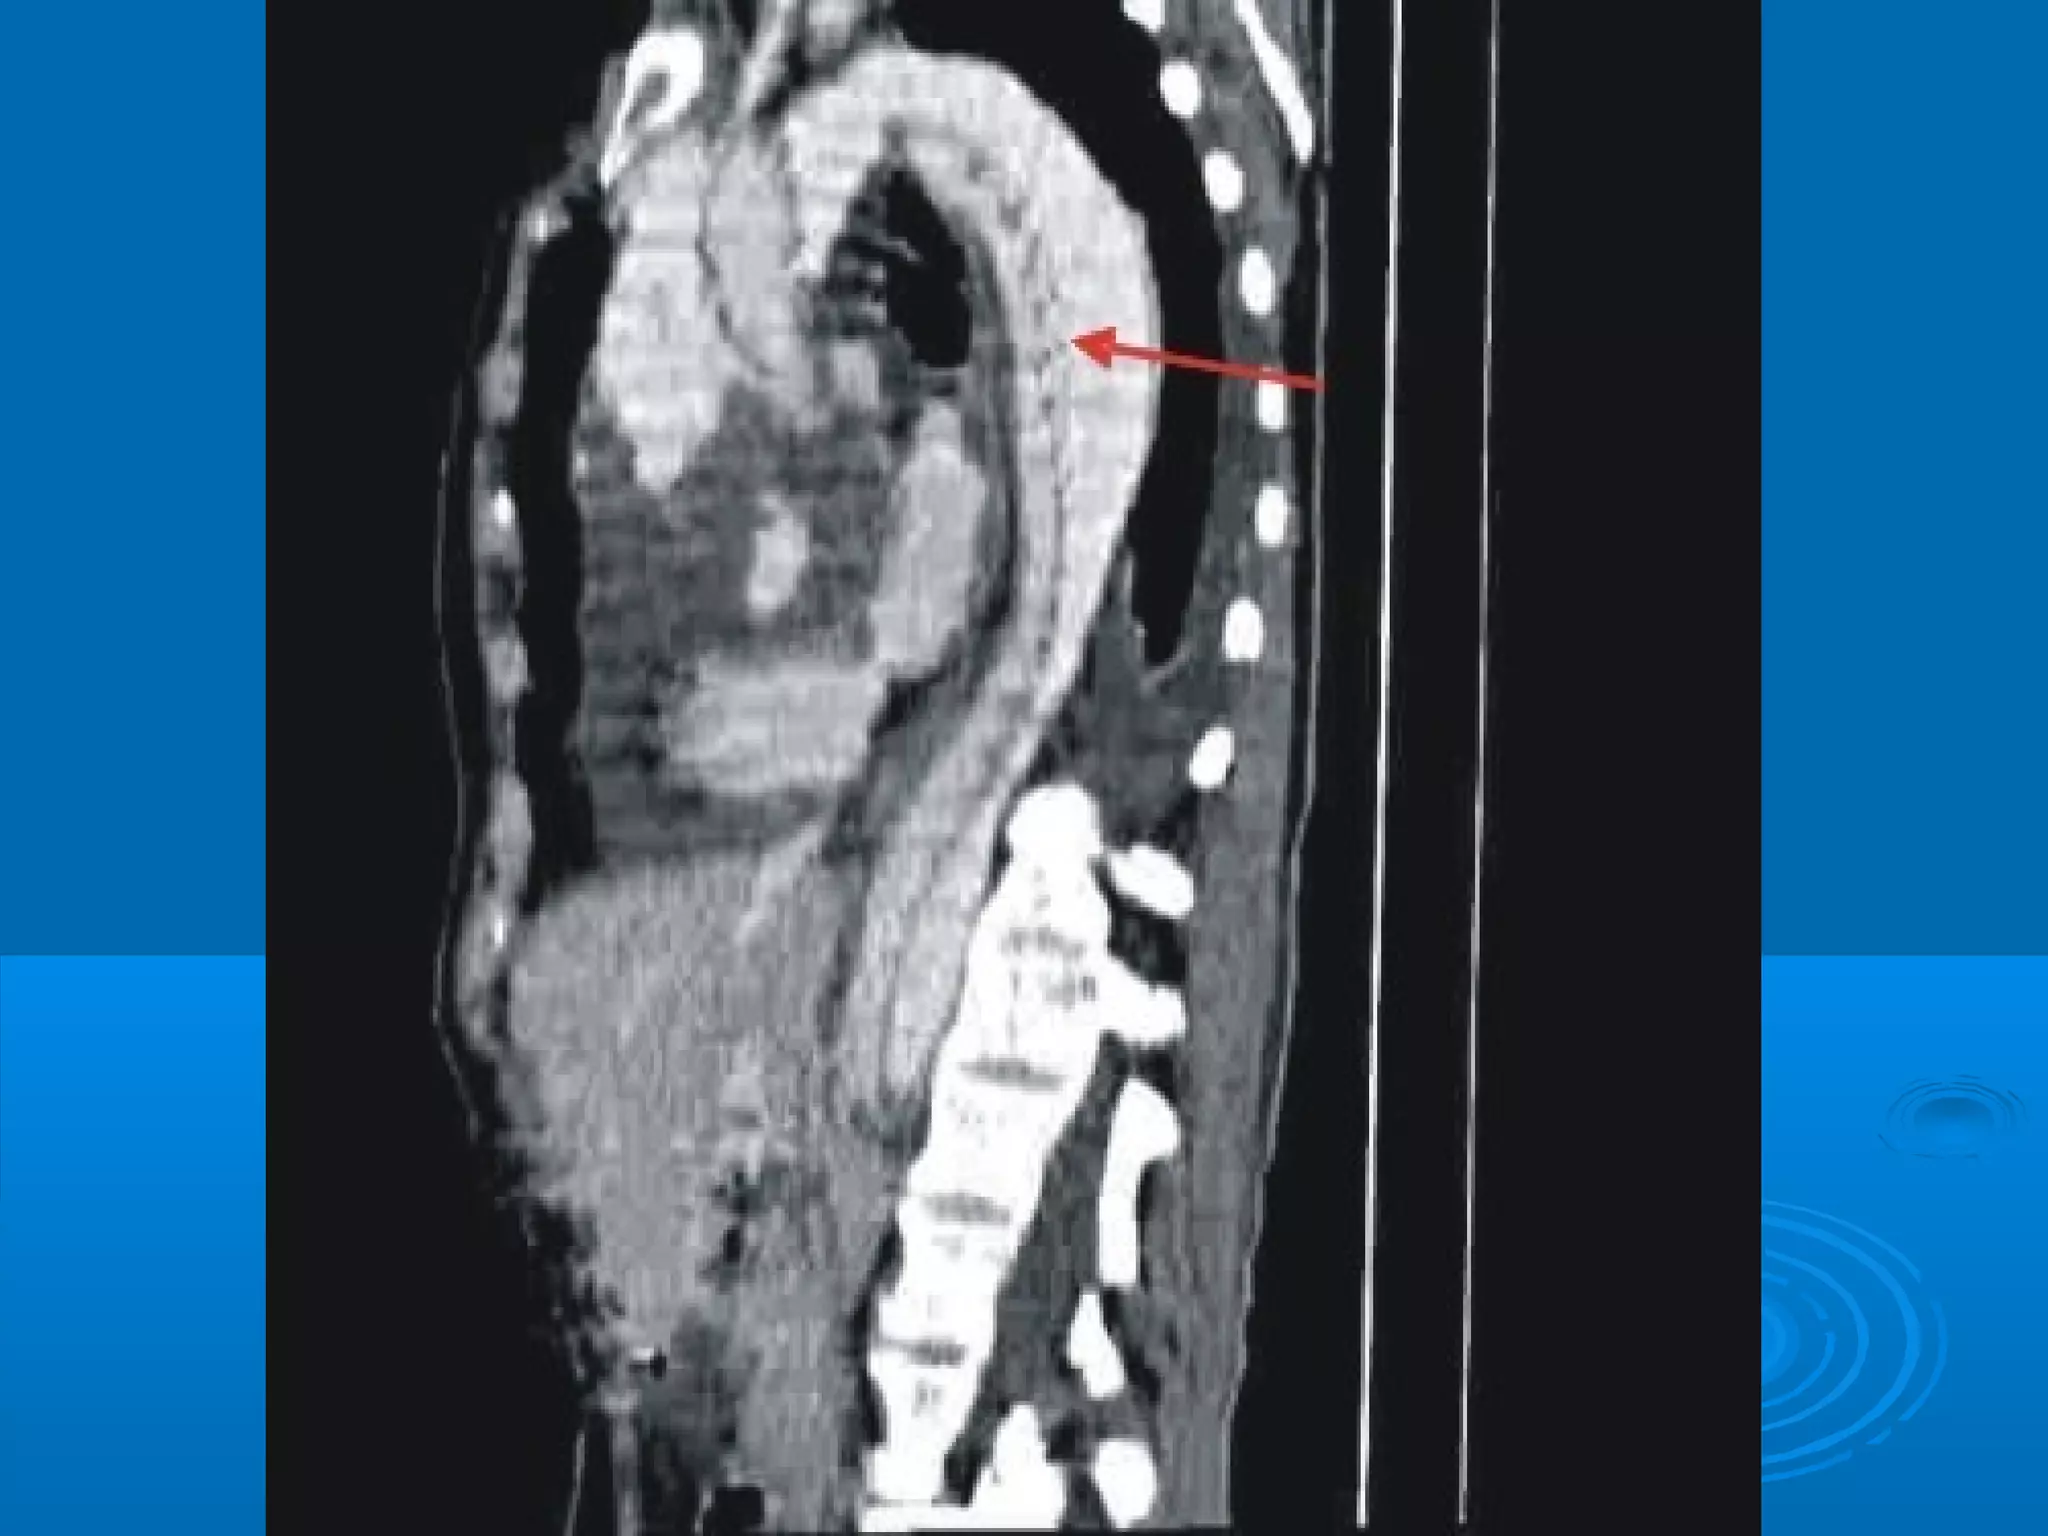

   TEM Abdominal

Exámenes complementarios:  Hemograma completo  Recuento de leucocitos  Aga y e-  EKG  Eco-abdominal  Rx torax y abdomen  TEM Abdominal  Bioquímica:  G-U-Cr  Proteínas totales y fraccionadas  Bilirrubinas TGO, TGP  Amilasa pancreática o lipasa pancreática, Fosfatasa alcalina, CPK (CPK - mb)  Examen citoquímico de orina